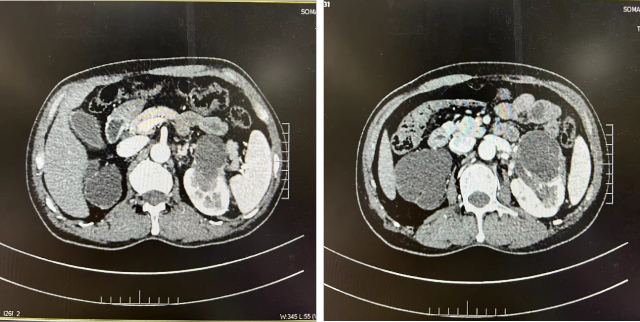

新辅助治疗前

新辅助治疗后

治疗后复查 CT(2022.7):左肾透明细胞 CA 治疗后改变,肿块较前缩小,强化程度减低,左侧副肾动脉可见;余况同前。